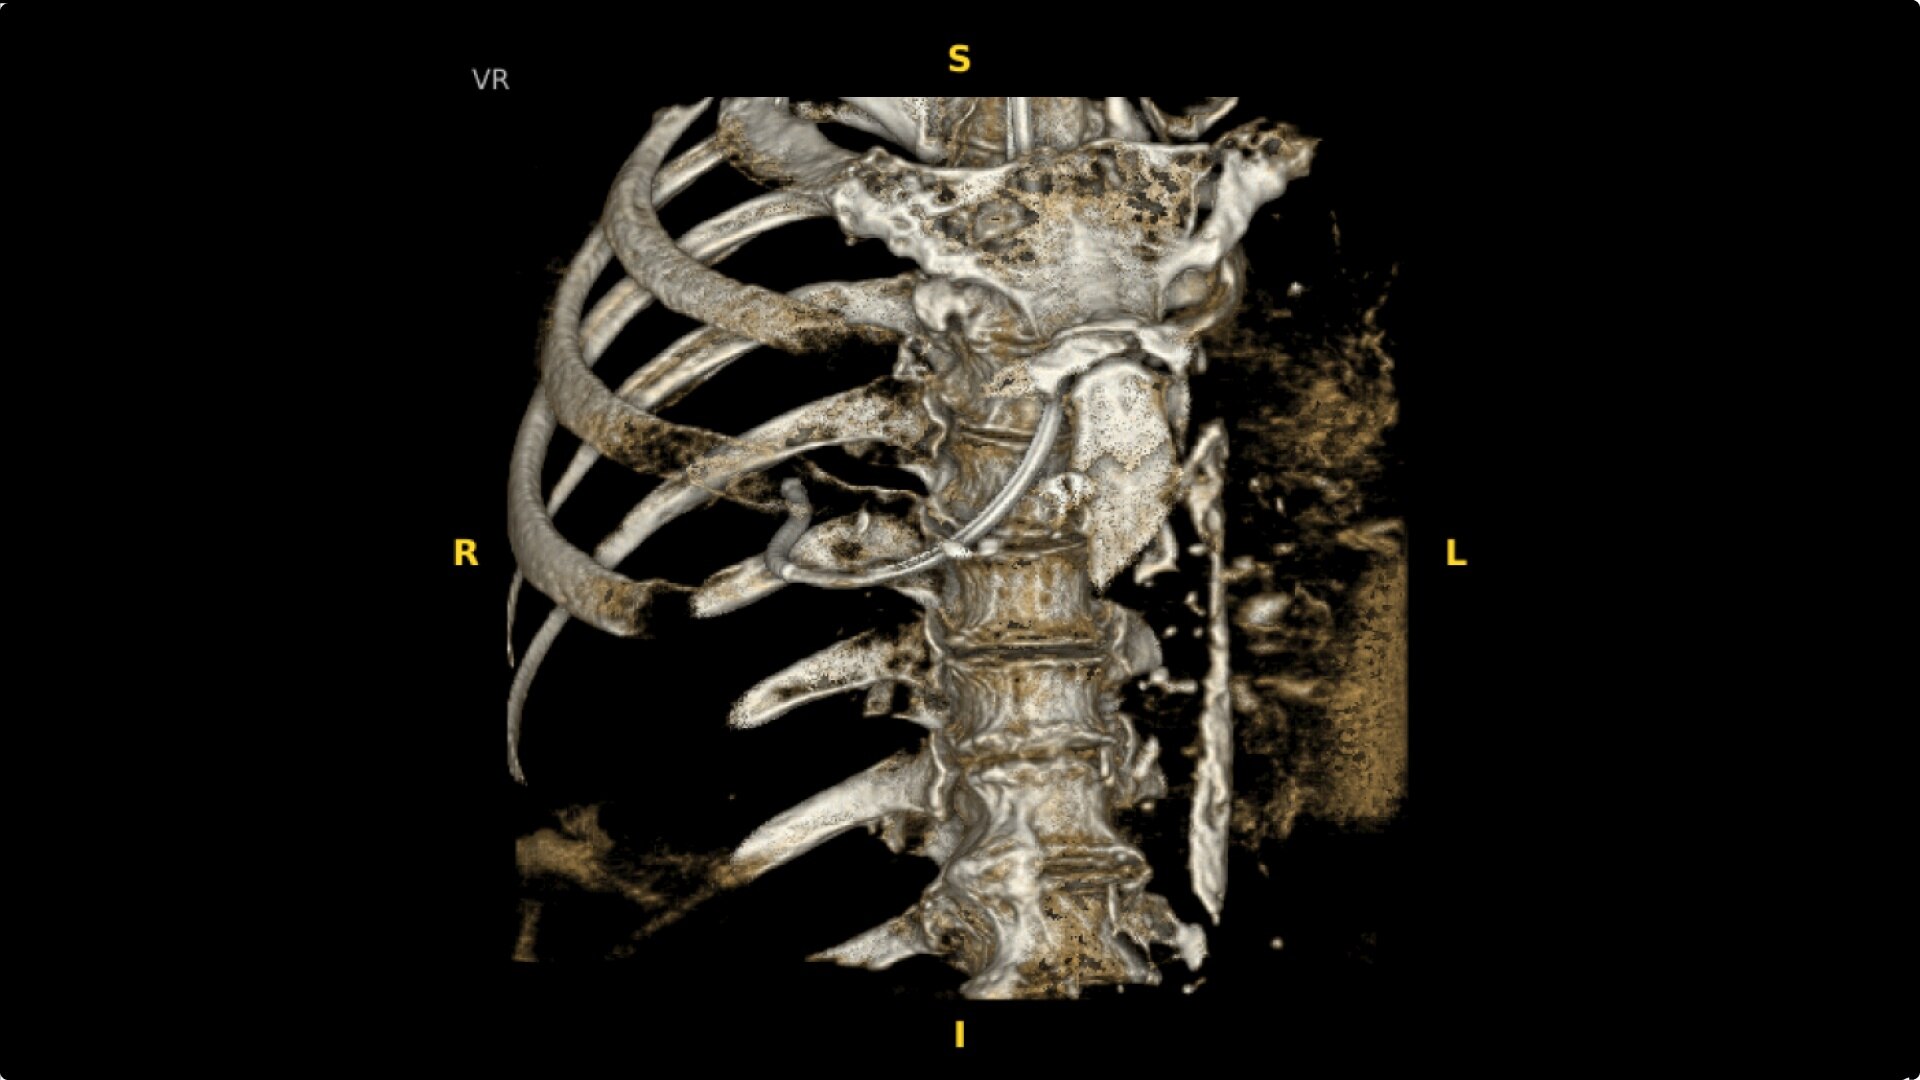

The OEC 3D provides comprehensive imaging with precise 19 cm x 19 cm x 19 cm 3D volumes and exceptional 2D images intraoperatively.

The OEC 3D presents five perspectives: Axial, Coronal, Sagittal, MIP, and VR, on a 4K display for clear and detailed review of 3D volumes and 2D images.

Augmented fluoroscopy aids visualization with ability to select point of interests in the OEC 3D CBCT volume and overlay on live fluoroscopy images. To accommodate patient and equipment positioning, the OEC 3D scan range is also adjustable for a simplified imaging workflow. Features available in Lung Suite application.